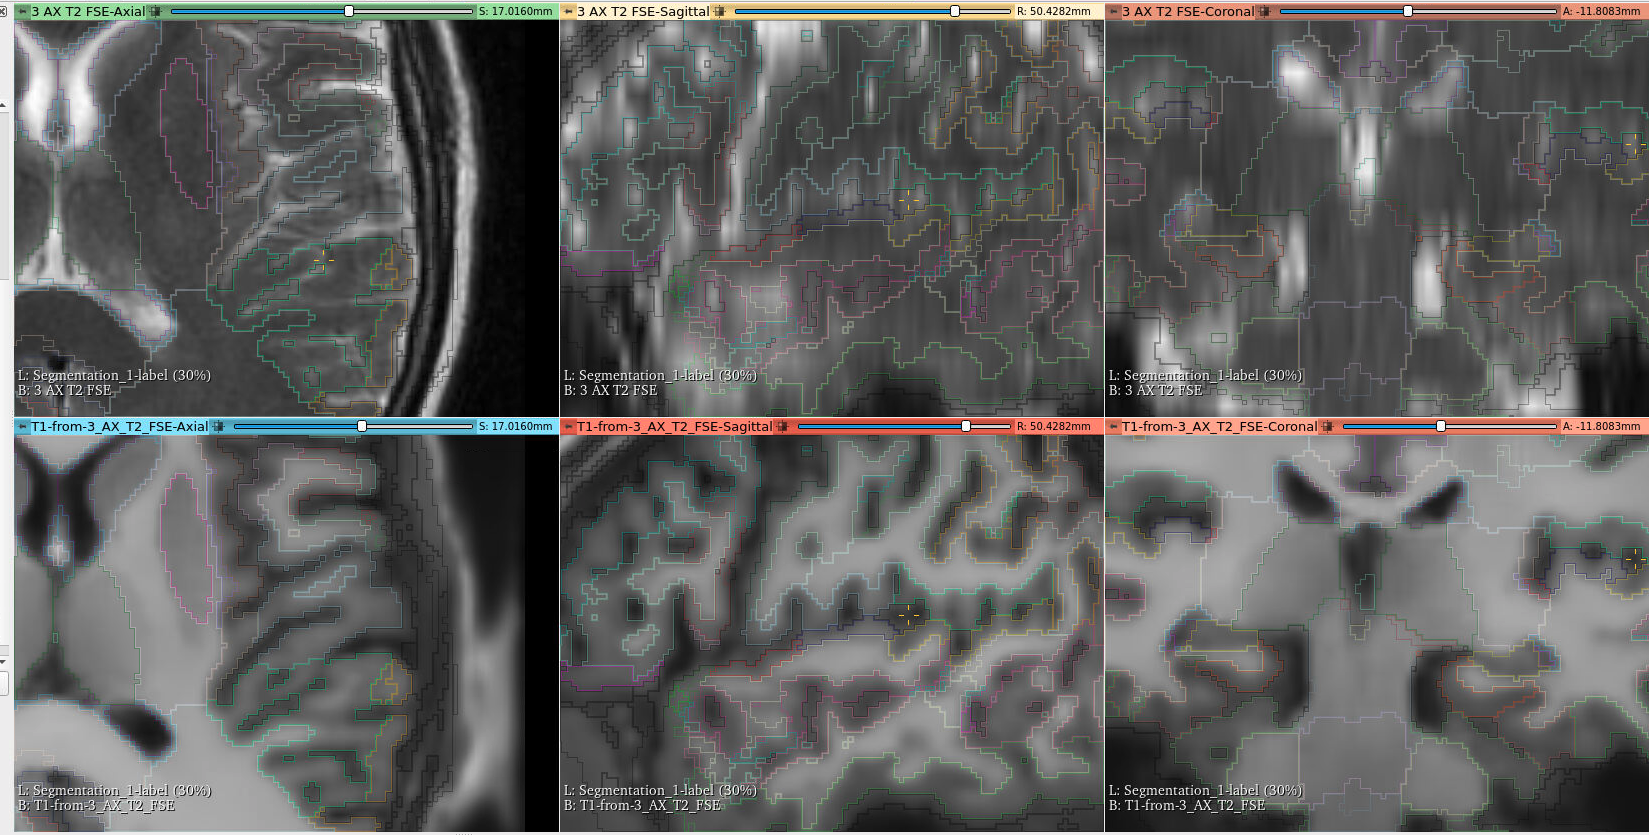

This is a parcellation run through the Imaging Data Commons framework, visualized online using OHIF: